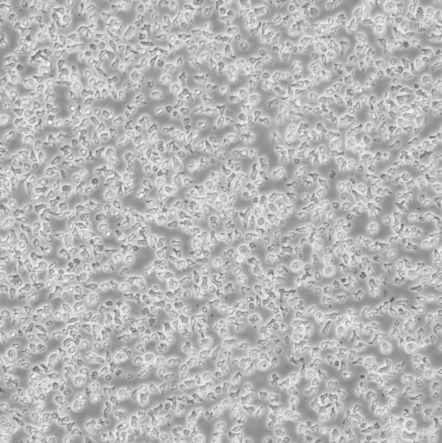

圆形,单个

SKW-3_成人急性T淋巴细胞白血病细胞

细胞名称:SKW-3_成人急性T淋巴细胞白血病细胞

种属来源: 人

性别年龄:男性,27岁

组织来源: 淋巴

生长特性: 悬浮生长

细胞规格: 1 X 106cells/T25或1 mL冻存管

培养条件: 90% RPMI 1640 + 10% h.i. FBS,37℃, 5% CO2